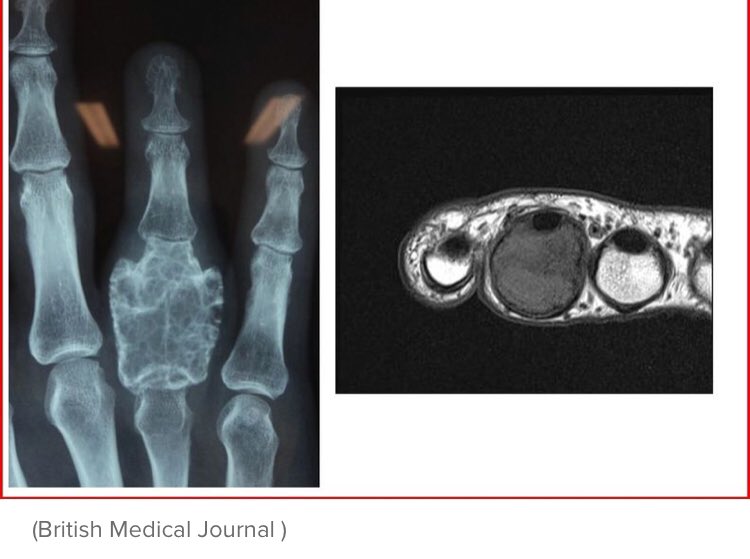

Ortopedi Doktoru در توییتر Orthopaedic Surgeons Replace Man S Fingerbone With A 3d Printed Part Https T Co Jlhdstchax Ortopedi De Onkoloji K Bir Vakada 3d Yazici Kullanimi Ile Ilgili Guzel Bir Vaka Ornegi Tip Orthopaedics